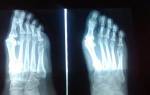

Боль под пальцами на ноге описывается как жгучая, ноющая. Она зависит от степени и разновидности артроза ступни. Кроме анализа анамнеза, диагностировать заболевание помогают лабораторные исследования (для определения воспаления), оценка размеров стопы, рентгенография. Визуализировать состояние хрящей, костей, мышц можно при помощи МРТ или КТ.

Врач оценивает появление симптомов со слов пациента, направляет его на рентгенографию, проводит измерение и оценку параметров стопы, использует методы плантографии и подографии. Степень плоскостопия устанавливается по результатам электромиографии.

Диагностировать остеопороз можно остеоденситометрии и рентгенографии костей стопы. При лечении требуется корректировать состояние, вызванное основным заболеванием, остановить или замедлить изменения в костной ткани, снять проявления боли в тканях конечности и в стопе под пальцами.

Требуется пройти рентгенографию.